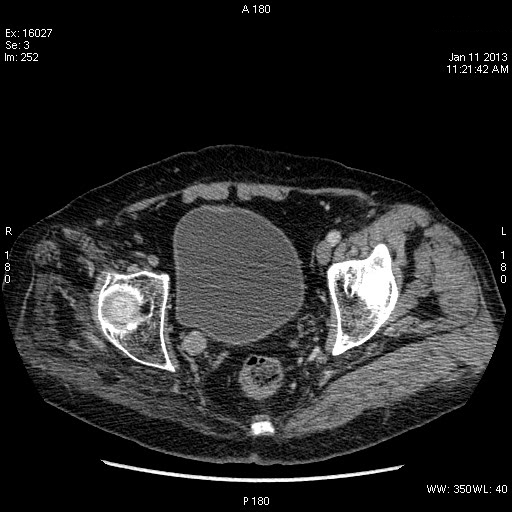

TCC нижней трети правого мочеточника

Да, переходноклеточная опухоль нижней трети правого мочеточника, вторичный гидроуретеронефроз.